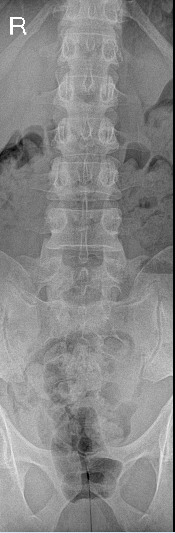

正位片

腰椎共6节。L6椎体双侧横突肥大,与骶骨形成假关节,符合腰骶移行椎(Castellvi IIb型)的影像学表现。